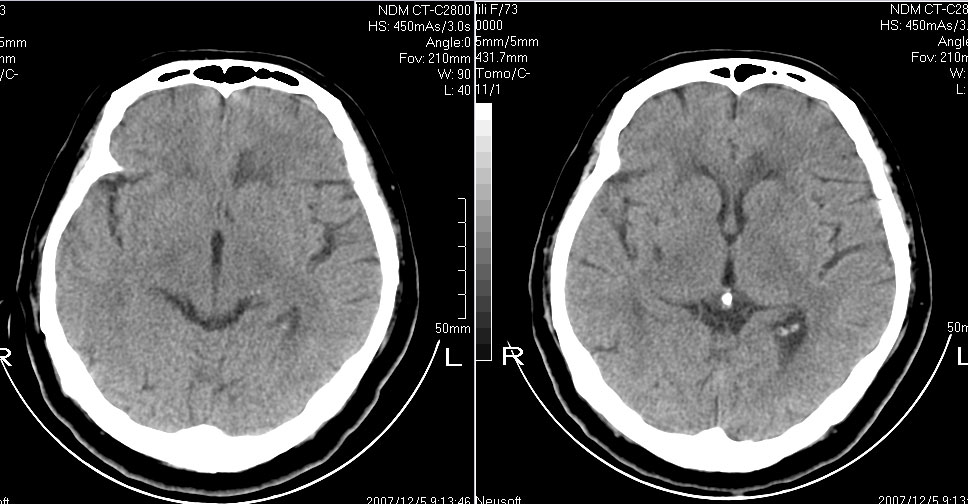

女,72,有高血压病史,突然寡言少语3日.

双侧基底节、胼胝体膝部多发腔隙性脑梗塞。

双侧基底节、左侧额叶 胼胝体膝部多发腔隙性脑梗塞。